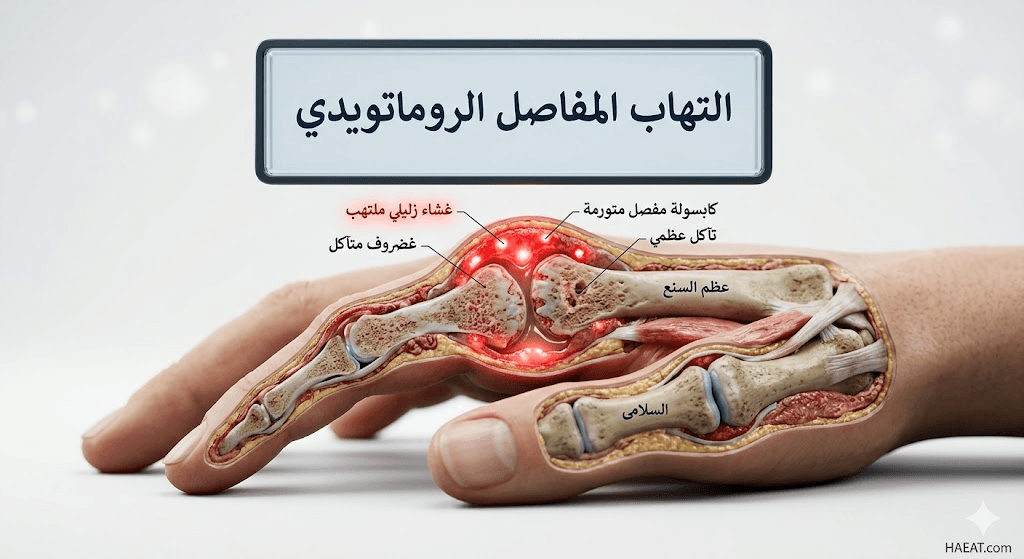

يعرف التهاب المفاصل الروماتويدي بأنه حالة مرضية يهاجم فيها الجهاز المناعي عن طريق الخطأ غشاء “السينوفيم” (Synovium) الذي يحيط بالمفاصل، مما ينتج عنه تضخم وسماكة في هذا الغشاء. يوضح موقع حياة الطبي أن هذا الالتهاب المزمن يؤدي في نهاية المطاف إلى تدمير الغضاريف والعظام داخل المفصل، مما يتسبب في ارتخاء الأربطة وضعف العضلات المحيطة.

- التورم والدفء المفصلي: تظهر المفاصل المصابة بـ التهاب المفاصل الروماتويدي بشكل متضخم ومنتفخ، مع شعور بحرارة موضعية عند لمس المنطقة المصابة نتيجة زيادة التروية الدموية للالتهاب.

- هشاشة العظام التآكلية: يؤدي الالتهاب المزمن واستخدام بعض الأدوية (مثل الستيرويدات) إلى إضعاف كثافة العظام، مما يجعل المريض عرضة للكسور التلقائية.